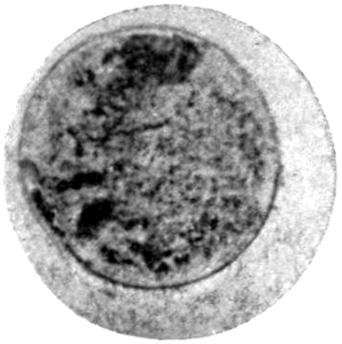

Plate III. 95

[43]

REFERENCES.

[1] Cloetta: Dixon Mann’s Forensic Medicine and Toxicology, p. 463.

[2] Oliver, Sir T.: Diseases of Occupation, p. 142.

[3] Goadby, K. W.: Departmental Committee on Lead Poisoning, etc., in China and Earthenware Manufacture, Appendix No. XXV.

[4] Meillère and Richer: Meillère’s Le Saturnisme. Paris, 1903.

[5] Blyth: Abstract of Proc. Chem. Soc., 1887-88.